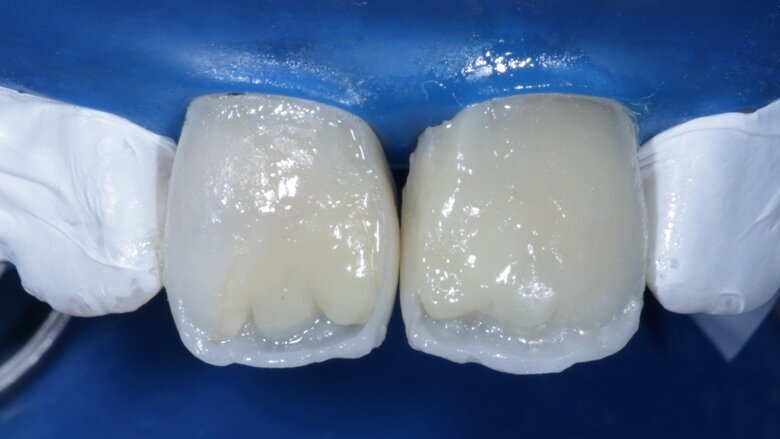

Two weeks later, the shade [ Fig 3 ] stabilized and the teeth were ready for bonding. We observed that the central incisors were still darker than the neighboring teeth. Direct composite veneers were planned with the help of a lab made wax up [ Fig 4 ] and a putty index. Bevels were placed and most of the preparation was in enamel. After the total etch protocol, 5th generation bonding agent was used. 3M Z350XT shades were used for the build up. A2 Enamel shade was used for the palatal shell [ Fig 6 ] and the proximal walls [ Fig 11 ].

Desaturation was achieved by layering a deeper darker dentin [ A3 Dentin - Fig 12 ] inside and a lighter dentin [ A2 Dentin - Fig 13 ] shade over it in the shape of three mamelons. Incisal Halo was achieved by layering an Achromatic Enamel [clear translucent] shade around the mamelons [ Fig 14 ] and the A2 dentin shade on the incisal edge [ Fig 11 ]. Final layer of A2 Enamel shade was used covering the restoration in 0.5mm thickness so as to avoid too much translucency [ Fig 15 ]. Finishing and polishing were done using the 3M Soflex discs and spirals [ Fig 17 ] as recommended by the manufacturer.

Fig 6 Enamel shade for palatal shell on putty index